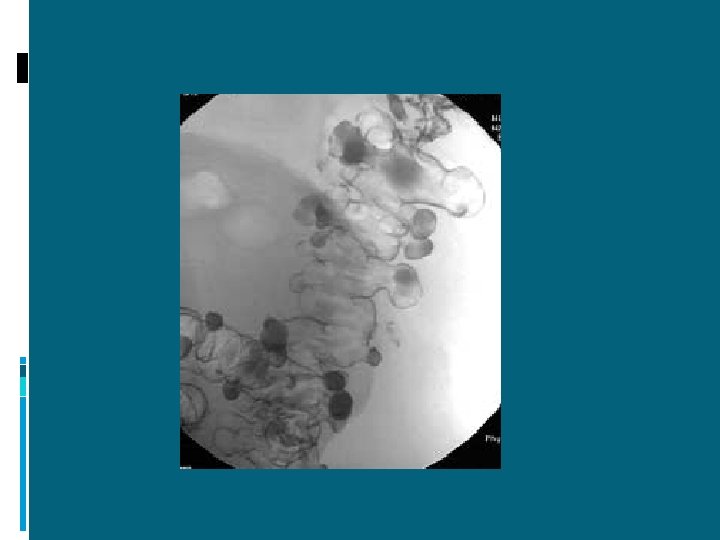

Peritonite diffusa purulenta

ADDOME ACUTO INFIAMMATORIO PERITONITI = “infiammazioni” della sierosa peritoneale

PERITONITI DECORSO ESTENSIONE EZIOLOGIA acute diffuse primitive croniche circoscritte secondarie terziarie

PERITONITI ACUTE DIFFUSE SECONDARIE A) PROCESSO PATOLOGICO (propagazione di processo infiammatorio o perforazione di organo cavo) : ulcera peptica perforata appendicite acuta colecistite acuta ischemia intestinale diverticolite neoplasia complicata pancreatite acuta altre